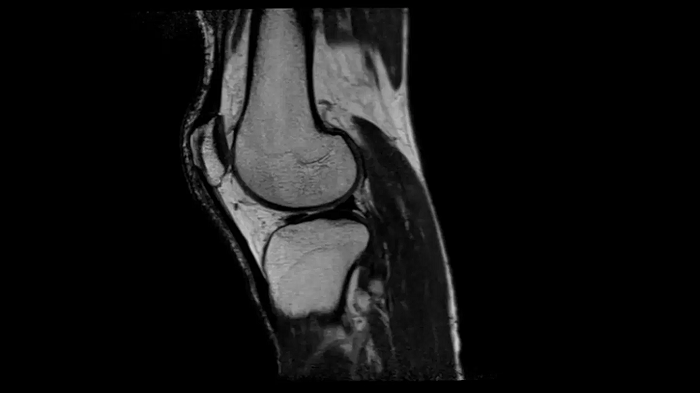

Knee

PD TSE Fat Sat with Deep Resolve and Simultaneous Multi-Slice

For clear imaging of the knee, outstanding fat suppression and performance are possible. Integrating the influence of Deep Resolve with the established Simultaneous Multi-Slice technique.

SMS 2 | Deep Resolve Gain & Sharp

0.4 x 0.4 x 3.0 mm2

TA 2:56 minutes

3D MSK Imaging with Compressed Sensing

Knee imaging with T2w SPACE can be expedited using Compressed Sensing to reduce acquisition times, offering high-resolution images for uncompromised knee assessments.

Compressed Sensing 6

0.3 x 0.3 x 0.6 mm2

TA 4:15 minutes

MAC-ID: 7aaaa0175. Image Credit: Siemens Healthineers